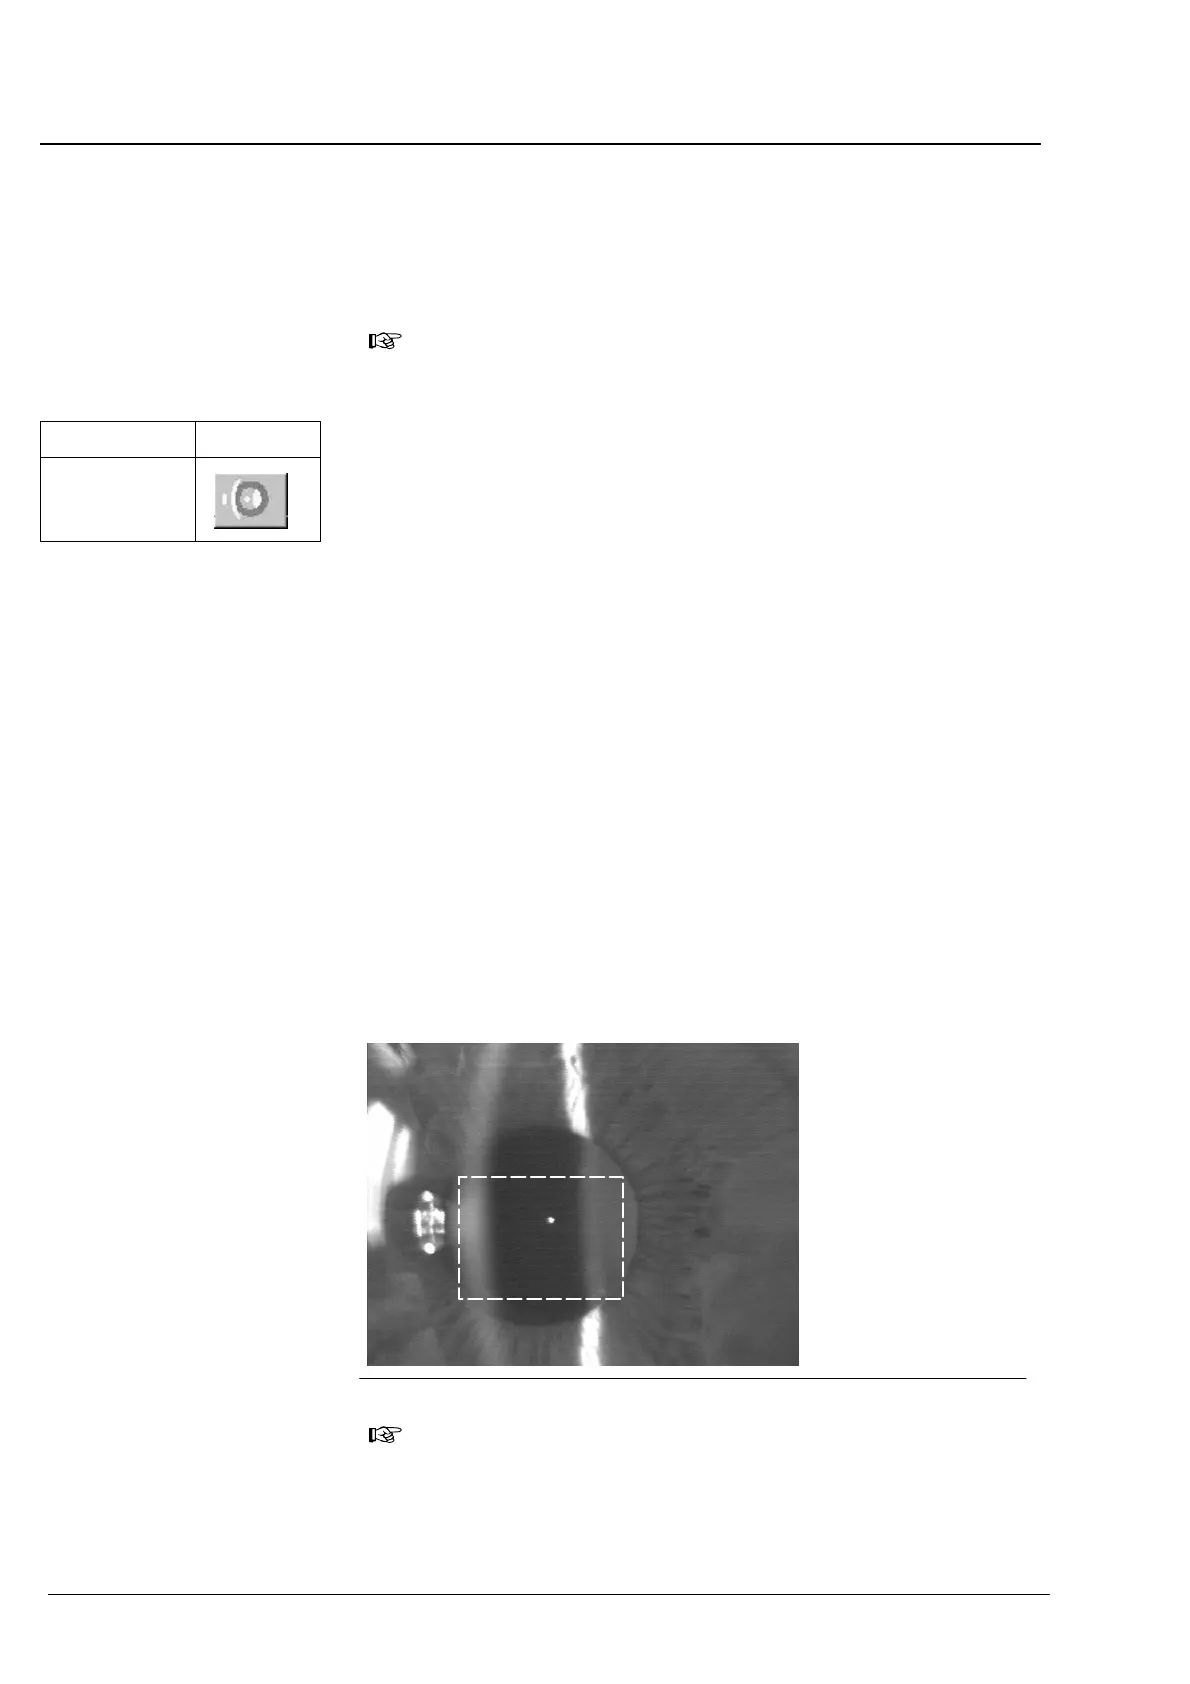

Réglage de précision de l'appareil de telle sorte que:

Ć l'image du point de fixation apparaisse de manière très nette dans

le rectangle sur l'écran,

Ć l'image de la cornée ne soit pas perturbée par des reflets,

Ć l'arête avant de la lentille soit visible de manière idéale!

En règle générale, l'image de point de fixation se trouve entre la cornée

et la lentille. Elle devrait se trouver le plus près possible de l'image de la

coupe de lentille (pas à l'intérieur)! Pour des raisons liées au système, la

cornée n'est pas représentée de manière précise.

Fig. 21 Réglage de la mesure de la profondeur de la chambre antérieure